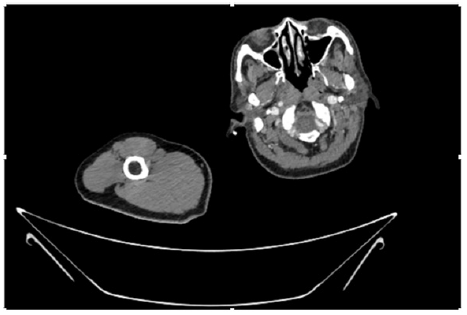

55-years-old chronic smoker had acute, severe pain in the right upper limb for one week; it was cold upto mid arm with skin discoloration. He also noticed numbness and weakness of movement of elbow joint. He underwent below elbow amputation in February 2023 for acute ischemia of left upper limb. He was a current chronic smoker; 15 pack year. General condition was weak; temperature was normal; blood pressure was 100/60mmHg; heart rate was 92/minutes with sinus rhythm; SpO2 was 97% on air; heart was normal. In lower extremities, all peripheral pulses were intact. Local Examination of right upper limb revealed as follows: tenderness; coldness; discoloration; decreased motor function and sensory modalities. Axillary, brachial and radial pulses were not palpable. Hand-held Doppler failed to detect any signal in arterial system; therefore, we arranged for emergency embolectomy. complete occlusion of right upper limb arterial system Full blood count showed high hemoglobin (14.6gm%); normal total WBC and platelet count. Coagulation profile was normal. Parenteral unfractionated heparin, antibiotics, tramadol, proton-pump inhibitors, anti-platelets and HMG CoA reductase inhibitors were given. Doppler ultrasound demonstrated complete occlusion of right upper limb arterial system. CT Angiogram illustrated occlusion of subclavian artery downwards on both sides. Figures 1-14 shows complete occlusion of right subclavian artery without collaterals. On Day ‘2’ of admission, the patient passed black tarry stool for 3 times. However, the vital signs were stable; blood pressure was 100/60mmHg; heart rate was 92/min; SpO2 was 97% on air; the abdomen was soft and not tender. Above elbow amputation was done on Day ‘2’ of admission. Intra-operative findings were as follows: (1) no active bleeding at brachial artery; (2) thrombosis along brachial artery; (3) muscle color and consistency were not healthy.

Figure 10: CT Angiogram at upper arm showing totally occluded right axillary artery; normal internal carotid artery and external carotid artery.